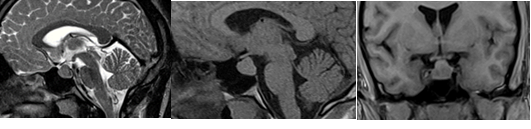

En la resonancia magnética de hipófisis contrastada con gadolinio se observó imagen hiperintensa de 14x15x11 mm, a nivel de la hipófisis. (Figura 1).

Se concluyó como un gigantismo acromegaloide por macroadenoma productor de hormona del crecimiento.